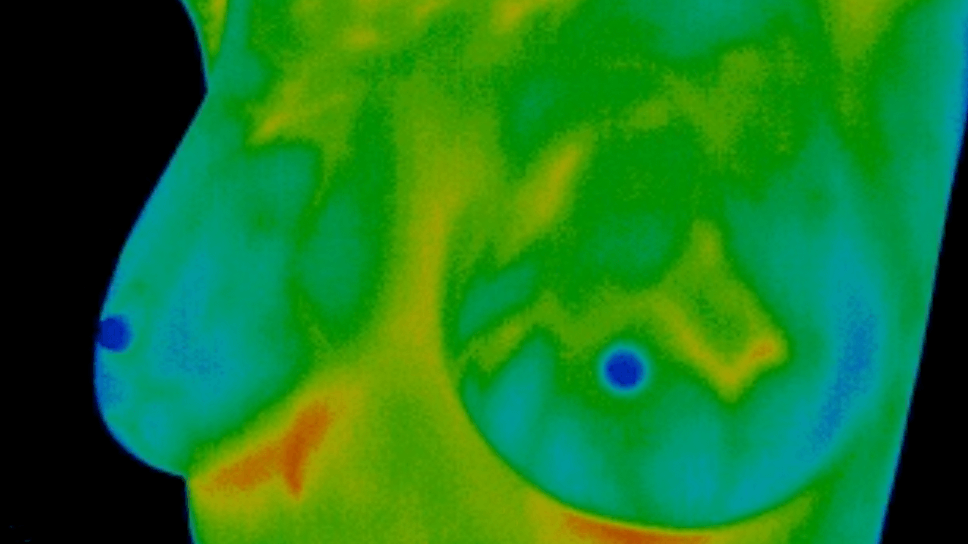

Pijnloos, zeer accuraat & betrouwbaar borstonderzoek

Medische Thermografie is een methode waarbij met een infraroodcamera foto’s van het lichaam worden gemaakt, zonder aanraking en zonder straling.

Deze keer een partner van Proud Boobs aan het woord over preventief thermografisch borstonderzoek. Een relatief nieuwe techniek om veranderingen in borstweefsel te registreren.